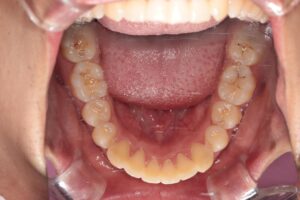

Before |

Before